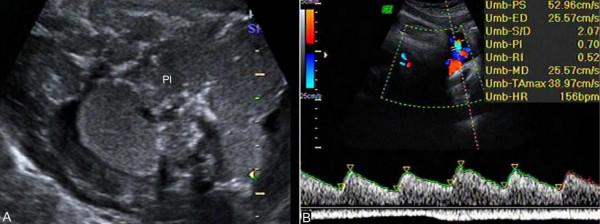

1.胎盤 超聲顯像檢查顯示Ⅲ級胎盤並不是胎盤老化、功能下降的徵象,如果無其他證據並且胎頭BPD>8.7cm時,常可以認為胎兒肺部已發育成熟。但過期妊娠時幾乎均是Ⅲ級胎盤(圖1A),這提示我們對於Ⅲ級胎盤的孕婦要排除過期妊娠的可能。Ⅲ級胎盤合併羊水過少和羊水渾濁,常提示胎盤功能低下,需要及時終止妊娠。

2.臍帶 正常妊娠時胎盤血液迴圈隨著妊娠月份的增加阻力逐漸下降,至妊娠40周時降至最低(圖1B)。過期妊娠時由於胎盤血管床的減少和間質纖維化增加了胎盤血液迴圈阻力,臍帶血流阻力增加,S/D升高。因此,超聲多普勒檢查過期妊娠的臍帶血流時,如果發現S/D不再降低反而升高,則提示胎兒宮內缺氧,並且臍動脈S/D的異常多發生在胎兒缺氧引起的其他改變以前。

圖25-22妊娠晚期胎盤及臍帶血流:A:Ⅲ級胎盤聲像圖 B:正常臍帶血流,S/D2.07